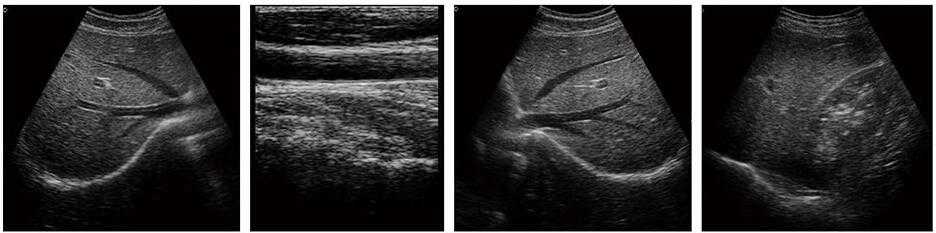

豐富的臨床應(yīng)用

多倍率顯示,病變?cè)\斷更精確